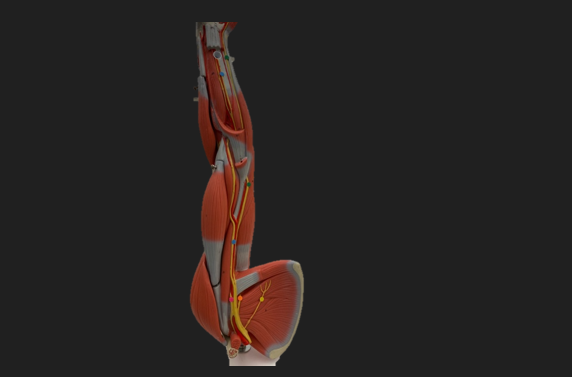

thoracodorsal n.

orange dot

axillary n.

pink dot

musculocutaneous n.

blue dot

median n.

green dot

ulnar n.

orange dot

radial n.

blue dot

deep branch of radial n.

green dot

superficial branch of radial n.

green dot

sciatic n.

pink dot

tibial n.

blue dot

common fibular n.

green dot

femoral n.

blue dot

deep fibular n.

green dot

superficial fibular n.